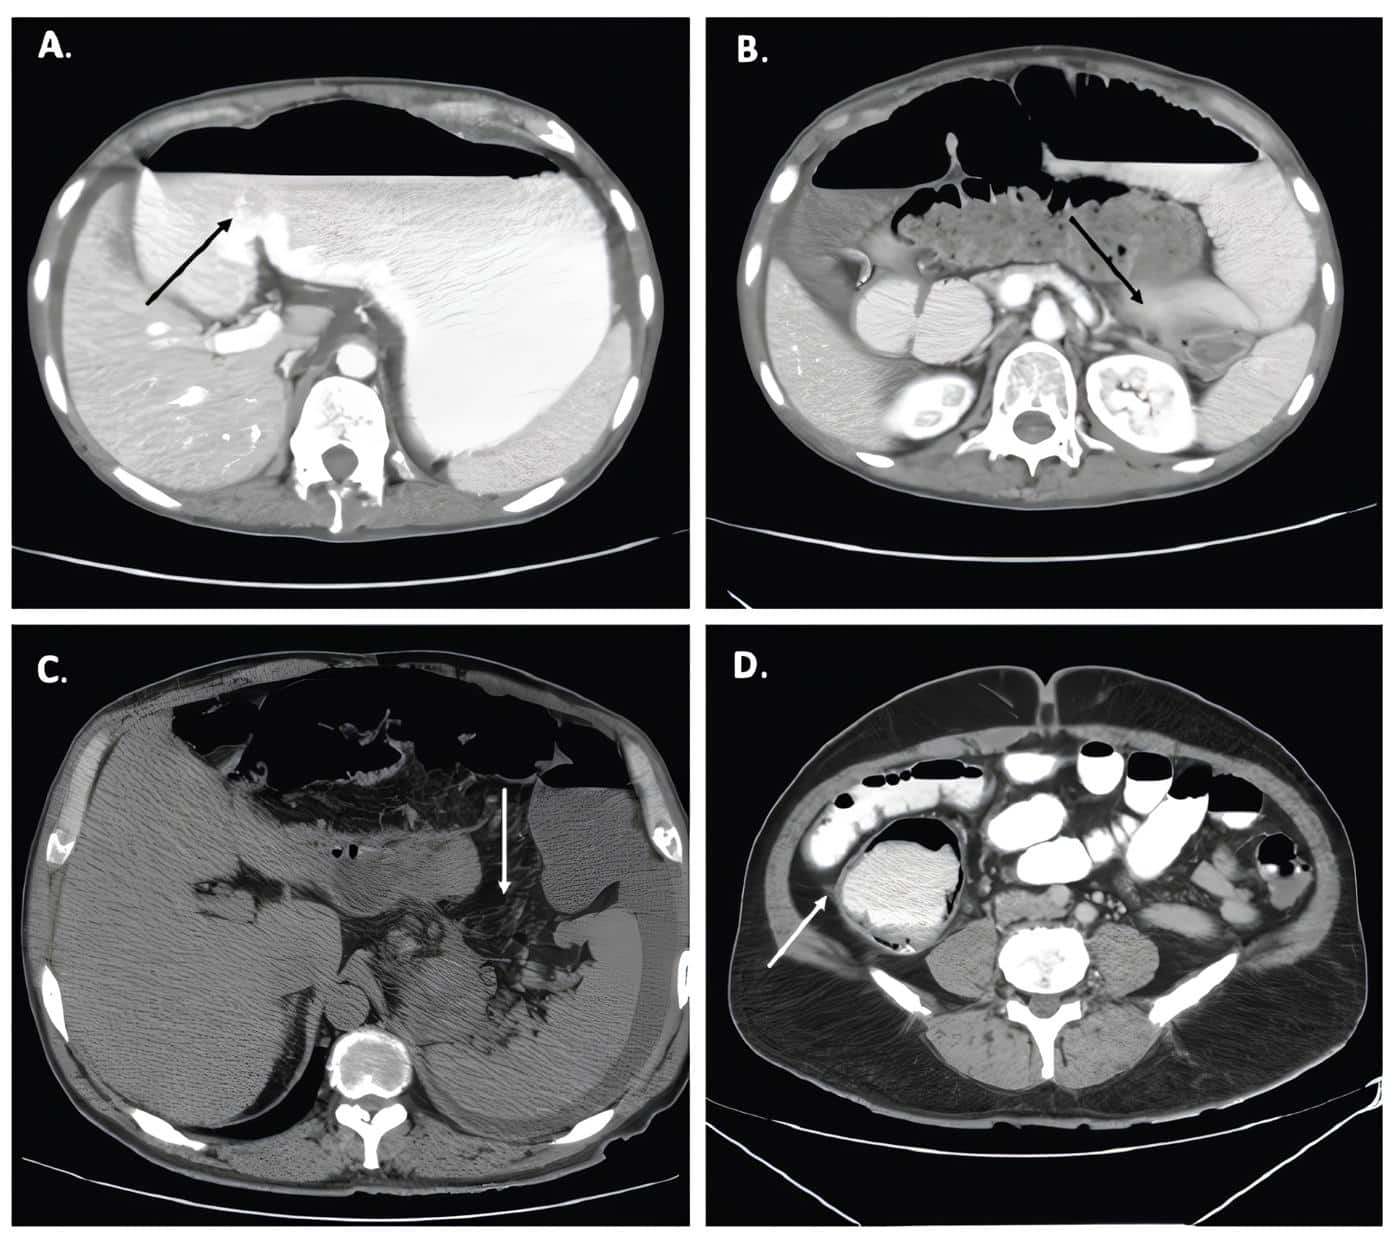

En la figura 2 se muestran algunos ejemplos de los posibles hallazgos en la tomografía abdominal. La identificación en la TC de una zona de transición es de vital importancia como un indicador de manejo quirúrgico, asociado a una ingurgitación de venas mesentéricas, el espesor de la pared intestinal mayor de 3 mm, la presencia de neumatosis intestinal, el edema mesentérico, el líquido libre intraabdominal y el gas en la vena mesentérica o porta, entre otros 10,11.

Figura 2. A-B. Dilatación de las asas intestinales delgadas con una zona de transición en el íleon terminal en la pelvis compatible con obstrucción mecánica. C. Distensión del ciego y colon ascendente con neumatosis y edema mesentérico asociado D. Tomografía de abdomen con evidencia de líquido libre.